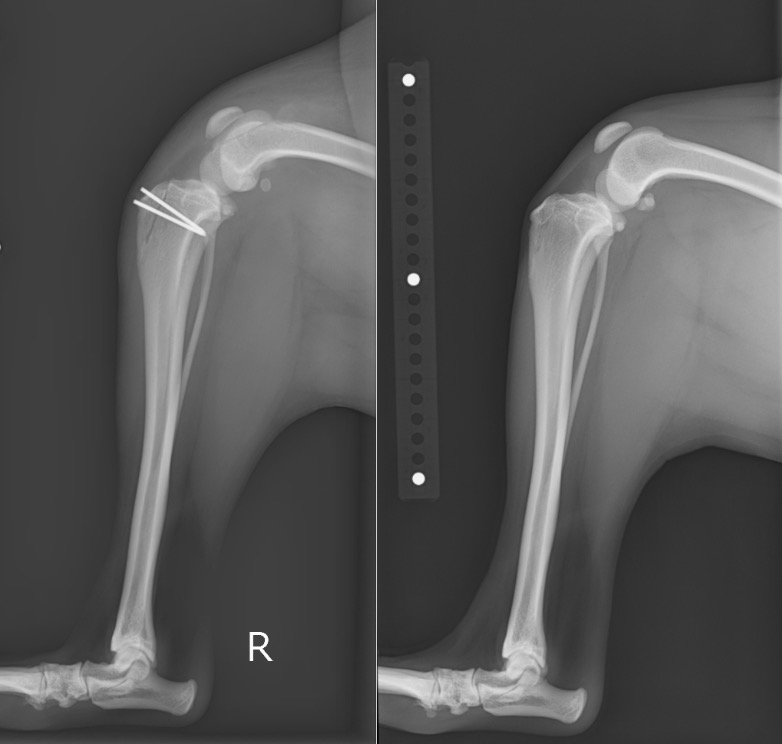

術前・術後のX線を見比べると、膝蓋骨が真ん中に整復されていることが分かります。

白く見えるのはステンレス製のピンであり、脛骨粗面転移という手技を行ったために使っています。

右後肢 【左:術後 / 右:術前】